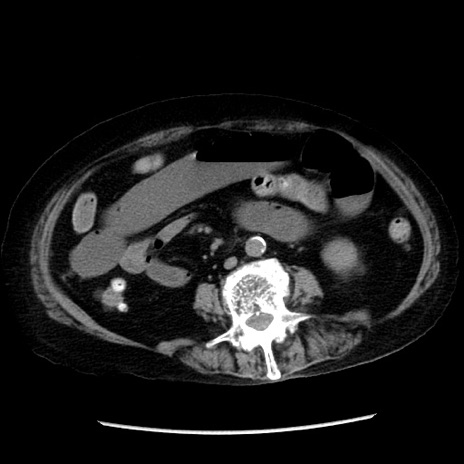

冠状断像

【症例】 90歳代女性

【主訴】 腹痛・嘔吐

【現病歴】今朝から左側腹部痛を認めた。 経過観察していたが、嘔吐を認めたため来院。

【既往歴】 子宮癌術後

【身体所見】 意識清明、BP 127/54mmHg、P 98bpm Sp02 95%(RA)、BT 35.8°C、腹部平坦・軟腸ぜん動音聴取良好、右下腹部圧痛(+) 反跳痛なし

【データ】WBC 9800、CRP 0.46